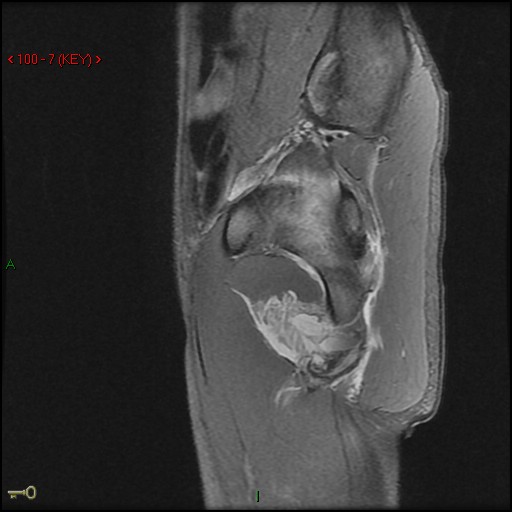

Figure 2 for case Ischial tuberosity ( RID2550 ) avulsion

Figure 2